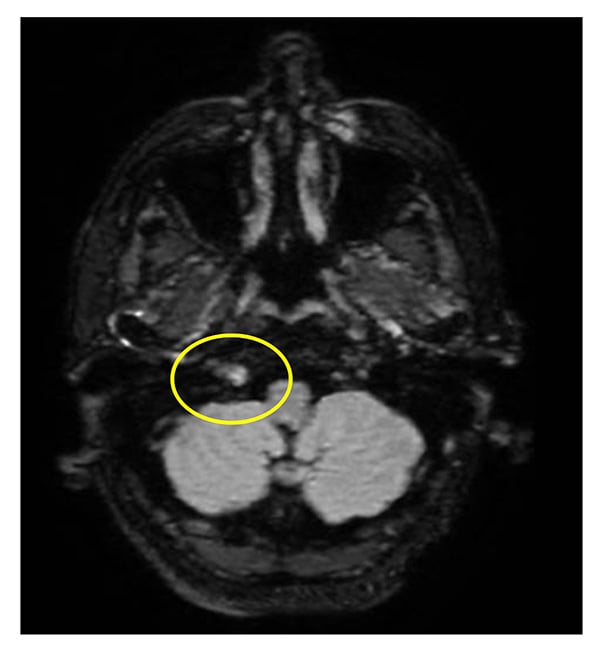

Three days later the patient developed dysarthria and was hospitalized. Neurologic examination found tongue deviation to the left, concerning for cranial nerve XII palsy. Laboratory evaluation revealed a neutrophilic leukocytosis with otherwise normal CBC, ESR, and CRP. MRI of the brain demonstrated hyperenhancement within the hypoglossal canal (Figure 3), which correlated with examination findings. Computed tomography of the chest, abdomen, and pelvis showed no evidence of malignancy. Lumbar puncture had normal cellularity and opening pressure and mildly elevated protein; tests including infectious workup, angiotensin-converting enzyme, oligoclonal bands, cytology, and flow cytometry were negative. Methotrexate 15 mg weekly with daily folic acid was added to prednisone and tocilizumab on discharge. Tongue deviation, dysarthria, and headaches resolved in the ensuing weeks and she continued to taper corticosteroids. Her course has been complicated by a deep vein thrombosis/pulmonary embolism, for which she was treated with low-molecular-weight heparin.

Figure 3: MRI of the brain at the time of hospitalization: post-contrast T2 fluid-attenuated inversion recovery (FLAIR) sequence shows T2 enhancement within the right hypoglossal canal.